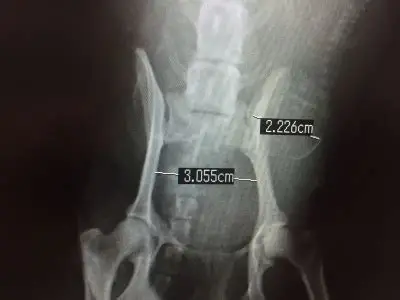

上記の理由から、分娩前には交配後55日でレントゲン検査を実施し、胎児の数や母体の骨盤の大きさを計測しておくことをおすすめします。

レントゲンでは

- 胎子の頭数

- 胎子の姿勢

- 胎子と母体の骨盤の大きさの比較

- 同腹胎子の成長の差

- 子宮内にガスがある

といったことを確認することができ、同腹胎子の成長の差や子宮内のガスは胎子が死亡している可能性を示しています。